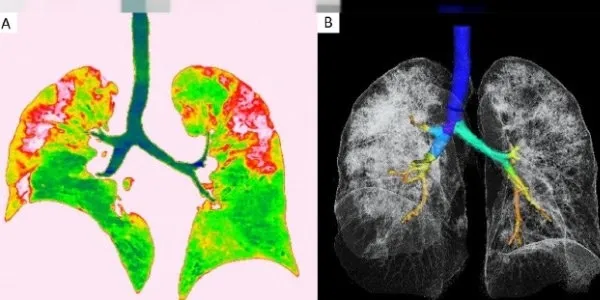

Koronavirüs belirti ve şiddetinin her hastada farklılık gösterdiğine dikkat çeken uzmanlar, hastalık sürecinin ağır geçirilmesinin nedenini, görevi vücutta virüsün çoğalmasını durdurmak olan Tip 1 İnterferon proteninin bulunmaması olarak gösteriyor.

Bazı kişiler Kovid19 için yaş ya da kronik hastalıklar açısından riskli grupta olmamasına rağmen bu hastalığı ağır geçirirken, bazı bireyler bu süreci belirtisiz ya da çok hafif atlatıyor. Kandan bakılan genetik bir testle bu konuda şimdiye kadar bilimsel olarak gösterilmiş tüm gen ve varyasyonların incelenmesi sağlanarak, hastalığı kimlerin ağır kimlerin hafif şekilde geçireceği belirlenebiliyor. Bu sayede kişi bir uzmana danışıp, Kovid19 konusunda alması gereken sosyal izolasyon, bireye özel tedaviler, bağışıklık güçlendirici uygulamalar gibi gerekli yaşam tarzı değişikliklerini hayatında yapabiliyor.

Prof. Dr. Özen, "Bireylerin genetik yatkınlığı ve geçmişi, bu hastalığın seyri konusunda önemli ipuçları veriyor. Kovid19'u çok ağır geçiren, yoğun bakım tedavisi görmek durumunda kalan hastaların bir bölümünde doğuştan gelen genetik mutasyonlara rastlandığı ortaya konuldu. Bu hastalarda vücudu virüslerden koruyan ve 10'dan fazla proteinden oluşan Tip 1 İnterferon bulunmadığı belirtildi.

Hastalarda koronavirüsün ağır geçirilmesinin nedeni de Tip 1 İnterferon sinyal ağının bozulmasından kaynaklanıyor. Kovid 19 Genetik Yatkınlık Testi ile bunu tespit edebiliyoruz" dedi.